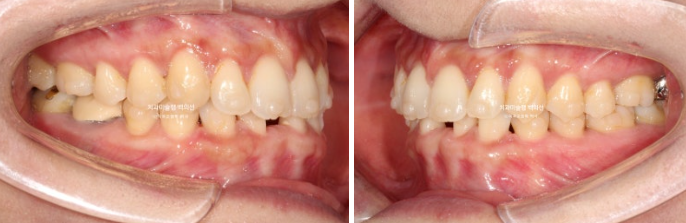

사진에 보이는 구멍은 앞니가 없어 송곳니가 앞니 자리로 이동하고 송곳니와 작은어금니 사이 공간이 벌어져 있습니다.

송곳니가 없는 것 처럼 보이지만 사실은 앞니 2개가 선천적으로 없는 상태입니다.

환자분이 모르고 있던 또 다른 문제는 파란화살표 제 2대구치가 혀쪽으로 쓰러져 있는 것 입니다.

빨간색 치축으로 표시한 치아가 쓰러진 치아입니다.

이 치아는 씹는데 중요한 역할을 하는 치아이므로 반드시 세워주는 것이 좋습니다.

그러려면 쓰러진 큰어금니 바로 뒤 썩은 사랑니는 빼주는 것이 좋습니다